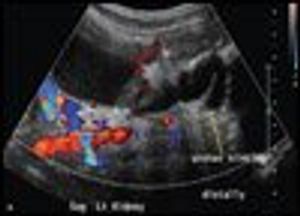

Vesicoureteral RefluxByBhargavi B. Kola, MD,Rajan Senguttuvan, MDJuly 6th 2010During hospitalization of a 6-month-old boy for respiratory syncytial virus infection, spiking fevers led to a bacteremia workup.